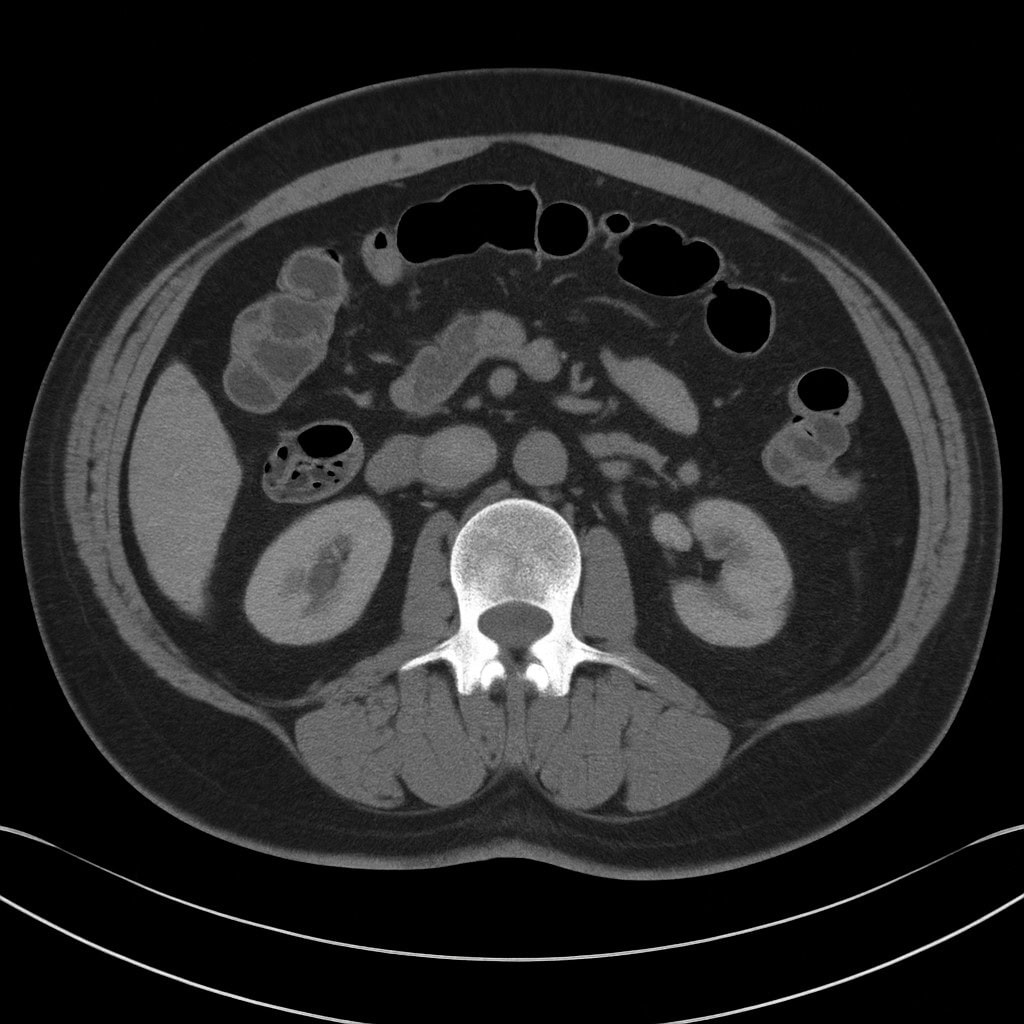

特に CT検査 は診断の中心であり、重症度の評価にも欠かせません。

🩺 なぜCT検査が“第一選択”なのか?

CT検査が大腸憩室炎の診断で重視される理由は次の通りです。

- 憩室炎に特徴的な所見(腸管壁肥厚・周囲脂肪織濃度上昇など)が明瞭に描出できる

- 膿瘍・穿孔・瘻孔などの合併症の有無と広がりを評価できる

- 虫垂炎や虚血性腸炎、大腸がん、炎症性腸疾患など、他の腹痛の原因疾患との鑑別に有用

- 人体への侵襲が比較的少ない検査でありながら、一度の撮影で多くの情報を得ることができる

腹痛を訴える患者さんでは、大腸憩室炎だけでなくさまざまな疾患の可能性があるため、

CTで炎症の部位と程度、合併症の有無を評価することが、

外来で経過観察とするか入院治療とするか、どのような抗菌薬治療を選択するかといった

治療方針の決定に直結します。

- 診断の中心はCT検査(重症度分類も可能)